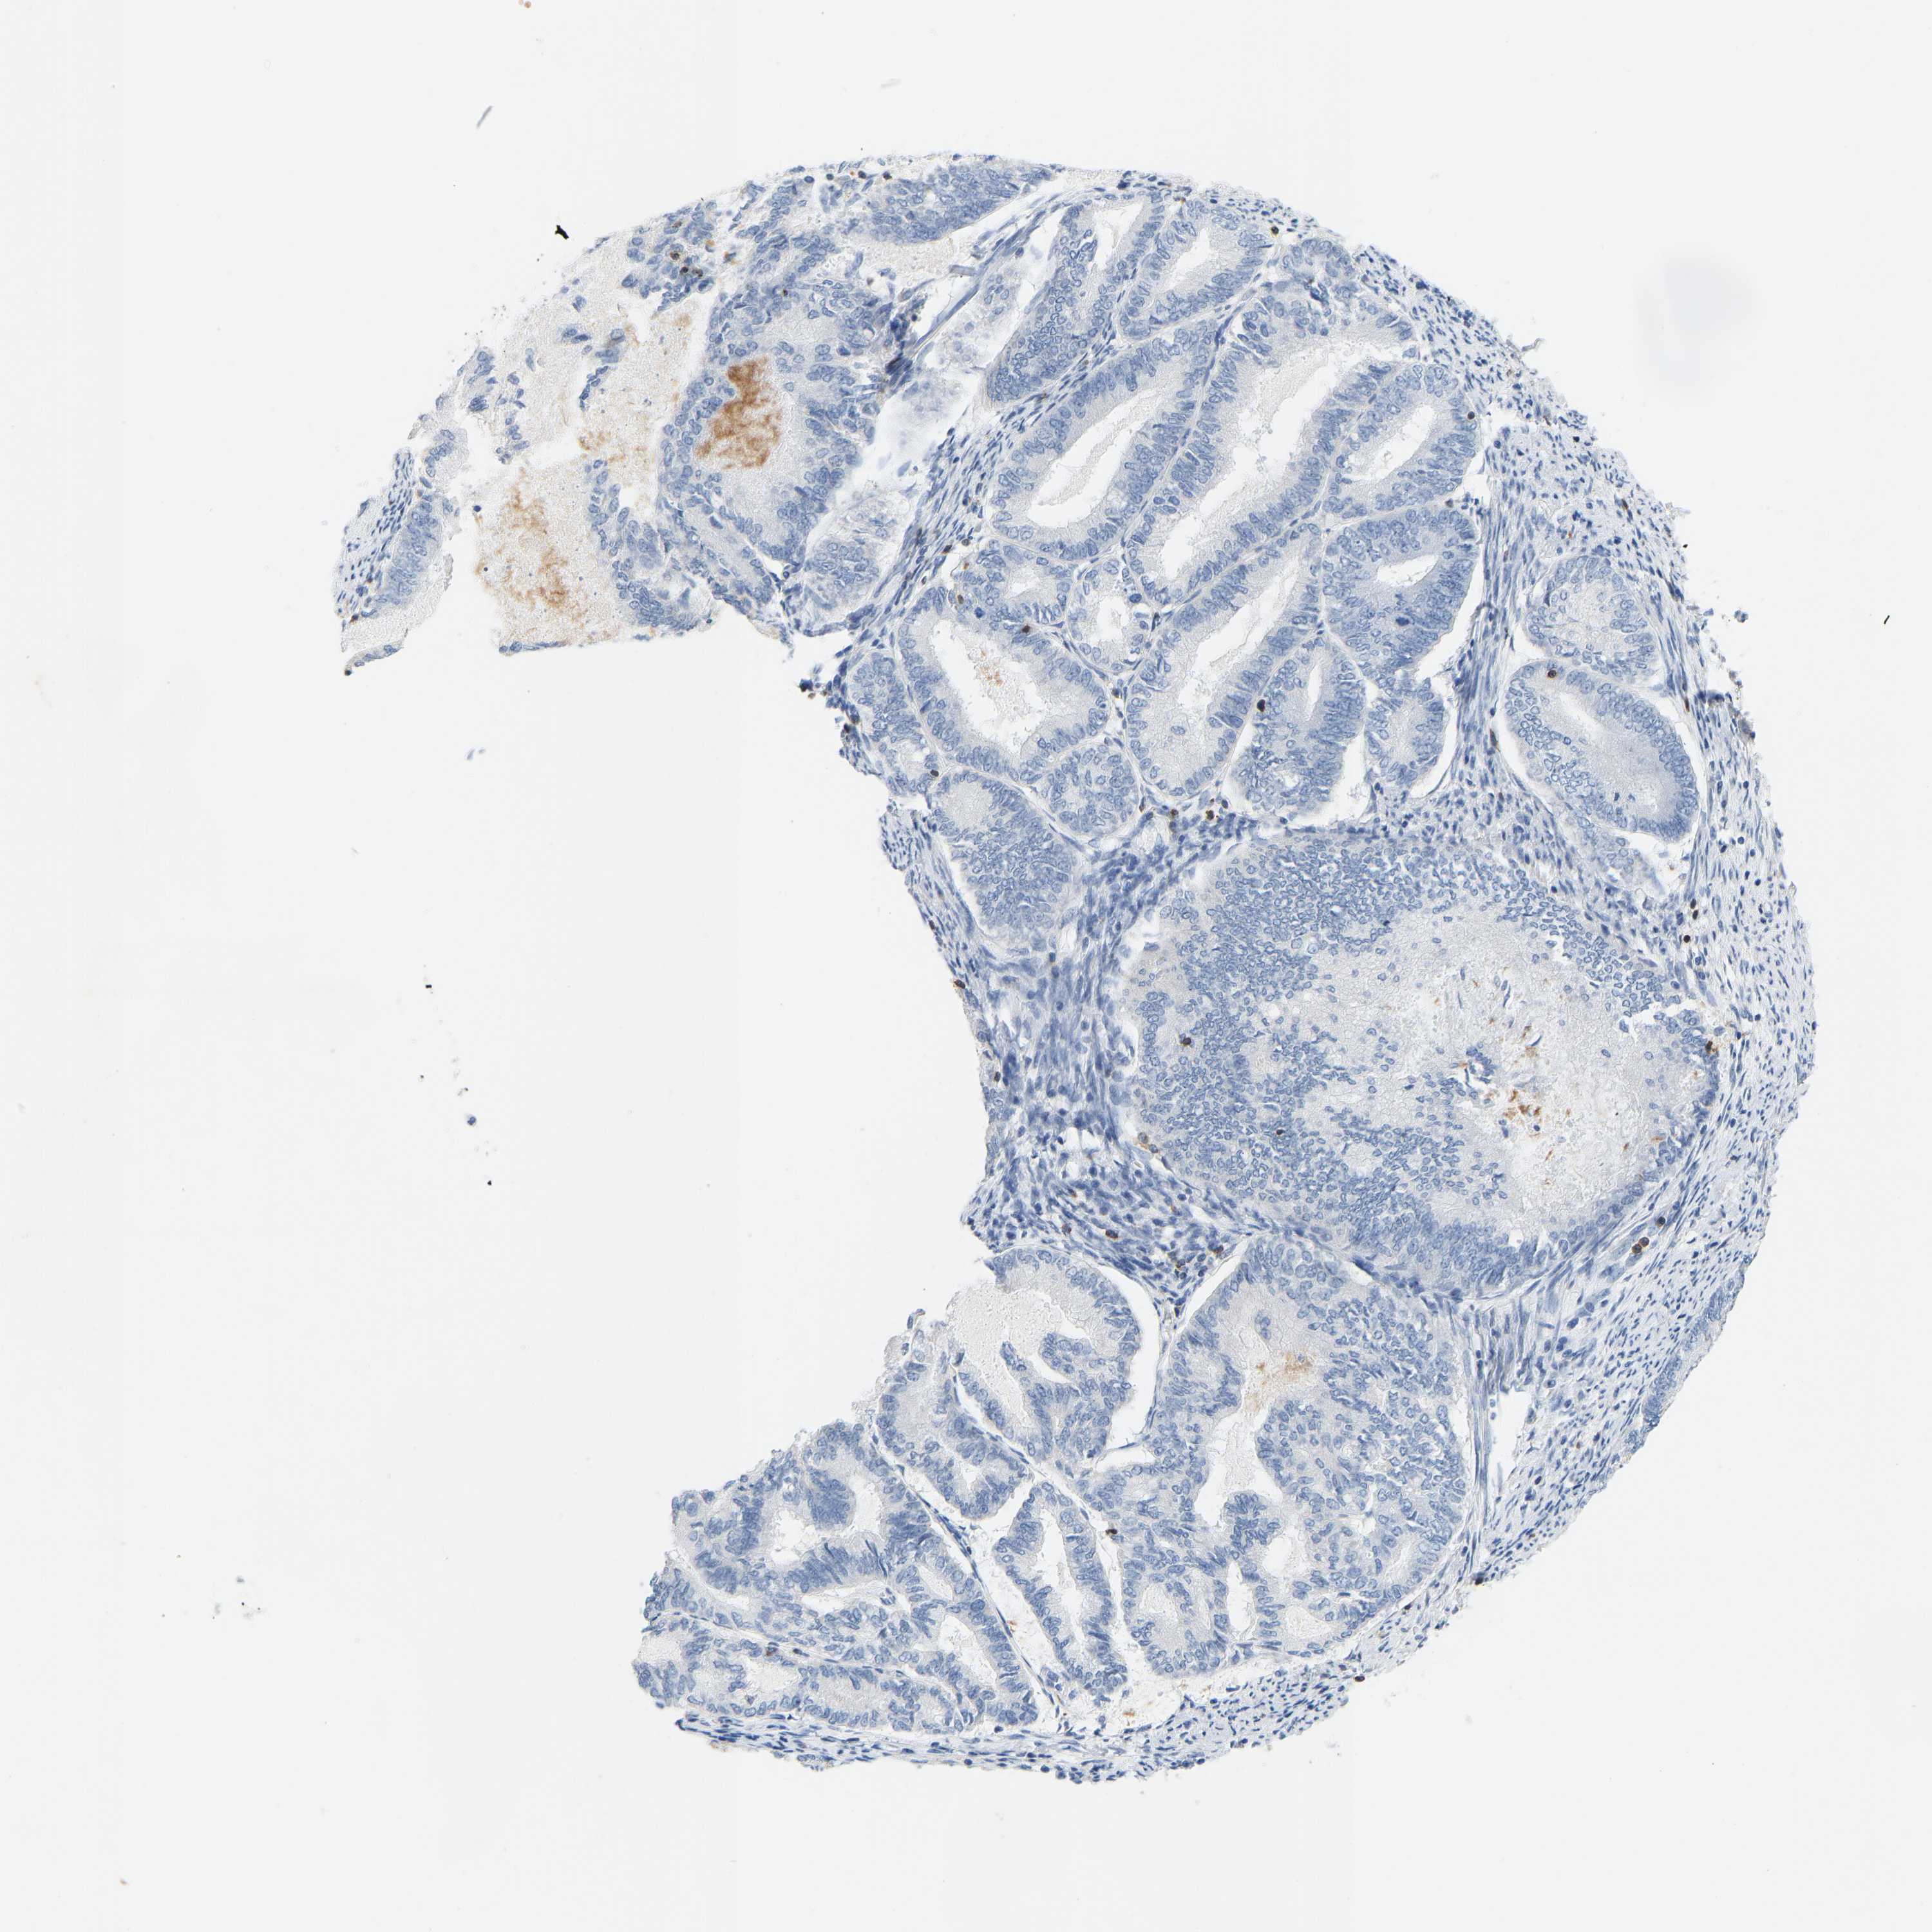

ENDOMETRIAL CANCER - Protein expressioni

A mouse-over function shows sample information and annotation data. Click on an image to view it in a full screen mode. Samples can be filtered based on level of antibody staining by selecting one or several of the following categories: high, medium, low and not detected. The assay and annotation is described here.

Note that samples used for immunohistochemistry by the Human Protein Atlas do not correspond to samples in the TCGA dataset.

Antibody stainingi

Antibody staining in the annotated cell types in the current human tissue is reported as not detected, low, medium, or high, based on conventional immunohistochemistry profiling in selected tissues. This score is based on the combination of the staining intensity and fraction of stained cells.

Each image is clickable and will lead to virtual microscopy that enables deeper exploration of all samples and also displays staining intensity scores, fraction scores and subcellular localization as well as patient and tissue information for each sample.

Antibody HPA018849

Antibody HPA019536

Antibody CAB033987

Staining

High

Medium

Low

Not detected

Intensity

Strong

Moderate

Weak

Negative

Quantity

>75%

75%-25%

<25%

None

Location

Nuclear

Cytoplasmic/membranous

Cytoplasmic/membranous,nuclear

Adenocarcinoma, NOS

Adenoma, NOS

Adenocarcinoma, metastatic, NOS